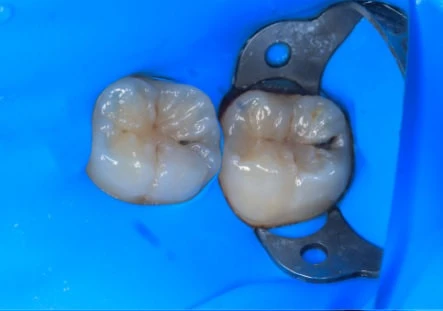

- Для реставрации жевательной поверхности зуба предпочтительным будет применение вкладки;

Процедура микропротезирования включает следующие этапы: